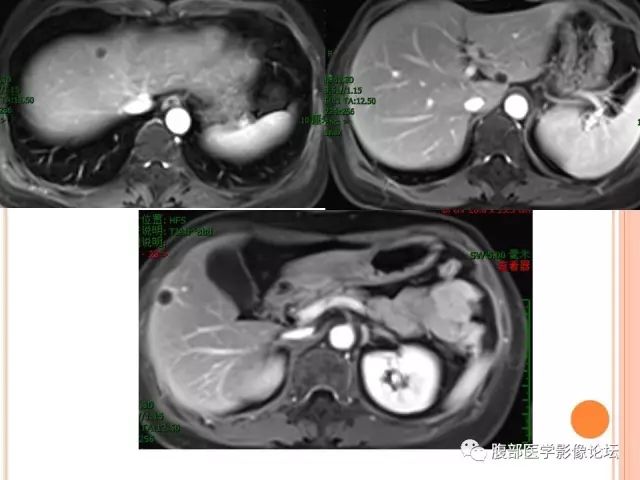

¢根据其在影像学中的图像特点,将肝脏孤立性坏死结节分为三种病理类型,分别为单纯凝固性坏死型、伴液化坏死型及多结节融合型 。

¢其中单纯凝固性坏死型的 CT平扫图像为低密度,MRI 增强扫描无强化。

¢伴液化坏死型的MRI T 1WI 扫描为低信号且其内为更低信号,T 2 WI 主要为等信号且其内高信号。

¢多结节融合型的 CT扫描图像为低密度,MRI 的 T 1WI 为低信号且其内稍高信号。

¢对比 CT 及 MRI 的图像特点病理分型发现,CT及 MRI 对肝脏孤立性坏死结节诊断结果相对一致且较为准确,在单纯凝固性坏死型病例中,CT优势略显著;在伴液化坏死型及多结节融合型中,MRI 优势略 显著。